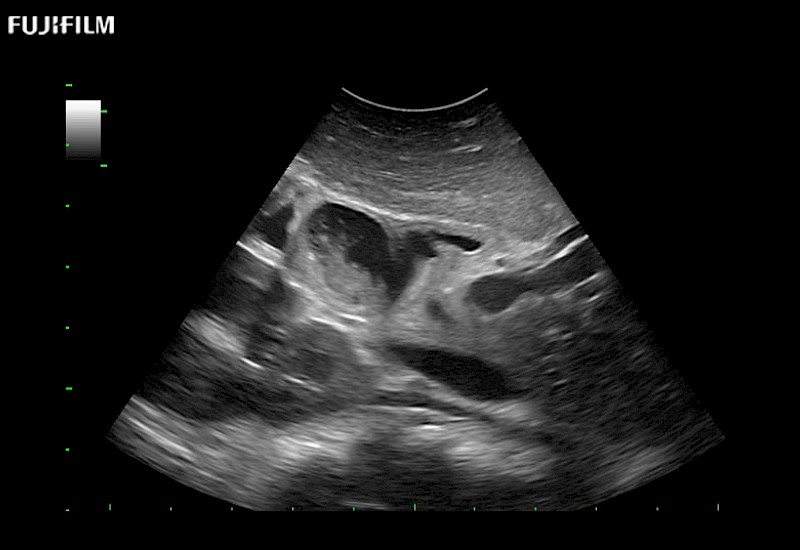

Extraordinary high-resolution digital imaging

for use during open and laparoscopic procedures: Tumor localization & staging, Ablation, Resection, Biopsy, Transplant, Abdominal exploration, Robotic surgery

- Instant feedback on tumor margin delineation

- Valuable information to guide tumor resections

- Instant feedback on tumor margin delineation

- Instant feedback on tumor margin delineation